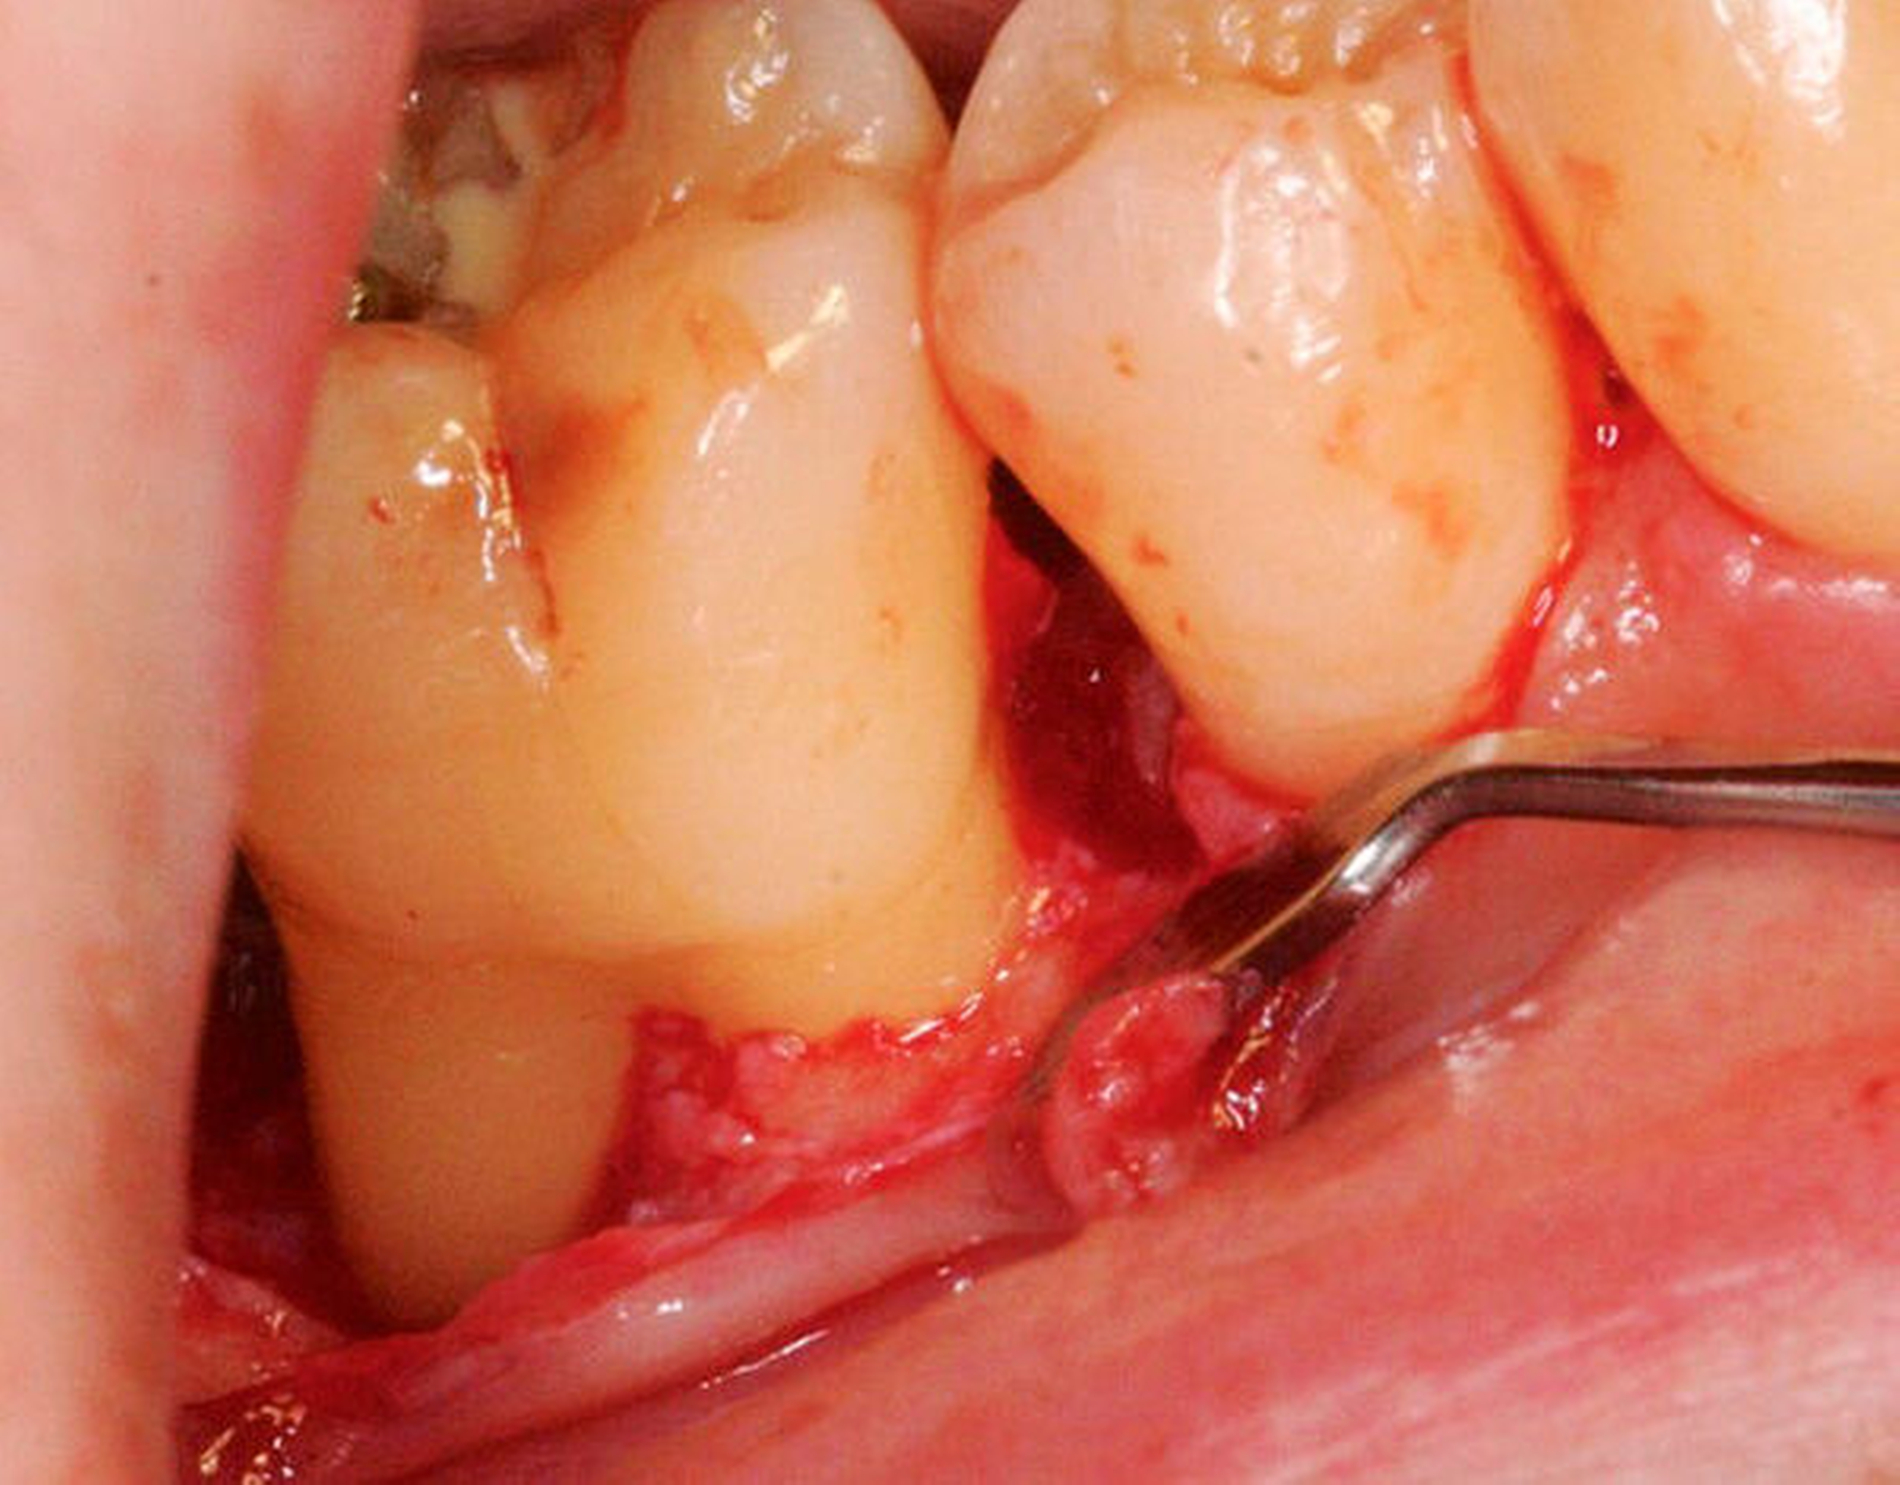

Den evidenzbasierten Empfehlungen der klinischen Leitlinie zu regenerativer Therapie von Knochentaschen (Abbildung 4) liegen 22 RCTs mit 1.182 Zähnen bei 1.000 Patienten zugrunde [Nibali et al., 2020]. In der Mehrzahl der Studien führte die regenerative Parodontaltherapie zu besseren parodontalen Parametern (höherer CAL-Gewinn und flachere Taschen) im Vergleich zur Instrumentierung unter Sicht (Zugangslappenoperation). Für den CAL-Gewinn wurde ein zusätzlicher Nutzen von durchschnittlich 1,34 mm (95 Prozent-KI: [0,95; 1,73]) und für die TST-Reduktion von 1,20 mm (95 Prozent-KI: [0,85; 1,55]) beobachtet. Das stellt eine Verbesserung von 80 Prozent (95 Prozent-KI: [60 Prozent; 100 Prozent]) im Vergleich zu den Kontrollgruppen dar. Ein mittlerer Unterschied in dieser Größenordnung wird als klinisch relevant erachtet, da damit das Risiko des Zahnverlusts reduziert wird. Beobachtungsstudien und experimentelle Studien, die sich mit Zahnüberlebensraten von 3 bis 20 Jahren beschäftigt haben, zeigten bessere Überlebensraten von Zähnen mit parodontaler Regeneration in regelmäßiger unterstützender Parodontaltherapie [Stavropoulos et al., 2021].

Was ist das adäquate Lappendesign für die regenerative Therapie von Resttaschen im Bereich von Knochentaschen?

Dieser Empfehlung liegen zwei systematische Übersichtsarbeiten zugrunde [Graziani et al., 2012; Nibali et al., 2020]. Durch einen Papillenerhaltungslappen lassen sich höhere CAL-Gewinne und TST-Reduktionen erreichen. Im Vergleich zur Instrumentierung unter Sicht (Zugangslappenoperation) führt diese Technik zu geringeren postoperativen Rezessionen. Die erhöhte Komplexität dieser Methode bedarf allerdings zusätzlichen Trainings. (Abbildung 4).